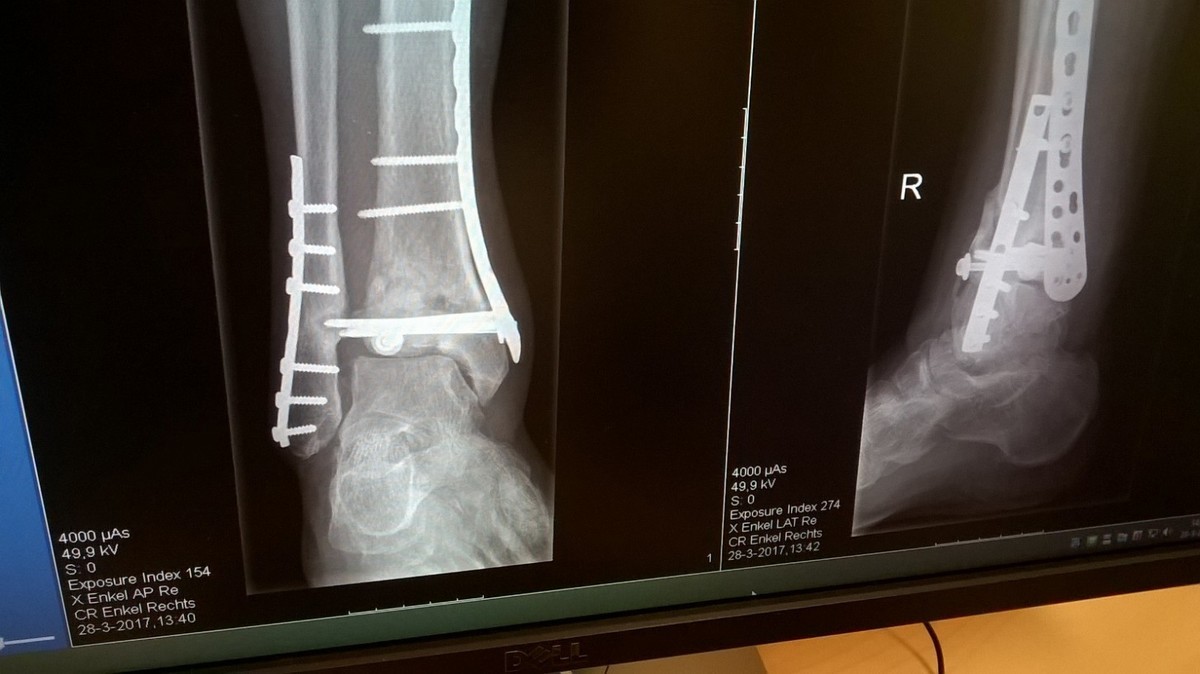

Vloeibaar kraakbeen? Kan me daar weinig bij voorstellen. Zou het niet misschien met synoviale vloeistof te maken hebben?Vloeibaar kraakbeen das super...en dat hecht aan je vaste / eigen kraakbeen?

Mocht je hier problemen mee hebben dan zal het vast niet verstandig zijn veel druk uit te oefenen op deze gewrichten. Wat hebben we ook een mooie sport uitgekozen.